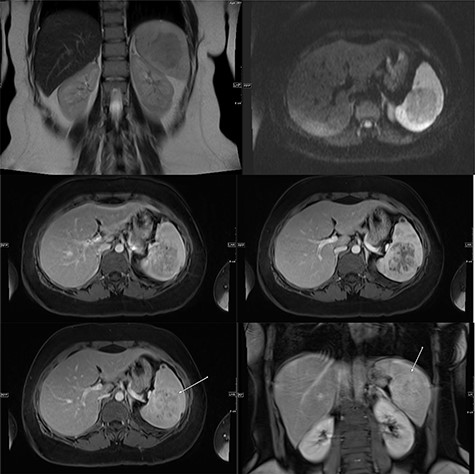

A multi-planar, multi-sequential abdominal magnetic resonance imaging (MRI) without contrast showed a well-circumscribed splenic mass with patchy nodular enhancement, which became more diffuse on delayed images and had low T2 signal and isointense T1 signal with no diffusion restriction (Fig. 3). There was no evidence of lymphadenopathy and no features favoring a lymphoma. The splenic mass was diagnosed as SANT, with plans to follow it with serial imaging.

(Top) coronal T2 WI MR Image showing a hypointense lesion in the spleen, which is not showing any diffusion restriction (right image); (middle images) post-contrast axial T1 WI MR image showing hypointense lesion with patchy contrast enhancement in the center (middle right image); the lesion becomes further isointense on delayed image (middle left image); (bottom) MRI of abdomen T1 weighted axial (bottom left) and coronal (bottom right) post-contrast images showing a lesion in the spleen (arrow) with peripheral and septal enhancement with a hypoenhancing center.